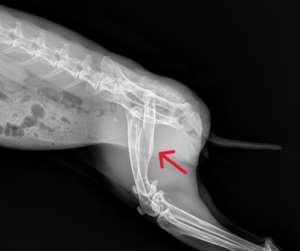

Osteosarcoma, or bone cancer, has been reported in domesticated rabbits. It is an uncommon cancer, diagnosed by x-ray imaging. Osteosarcoma is malignant and capable of metastasizing to other organs. The condition is characterized by hyperplasia and bone lysis. Affected bones will look perforated and misshapen on an x-ray due to the breaking down and overexpression of skeletal tissue.

This neoplasm can occur in various bones or joints, such as the glenohumeral joint, intertarsal joint, sacrococcygeal joint, and rib.